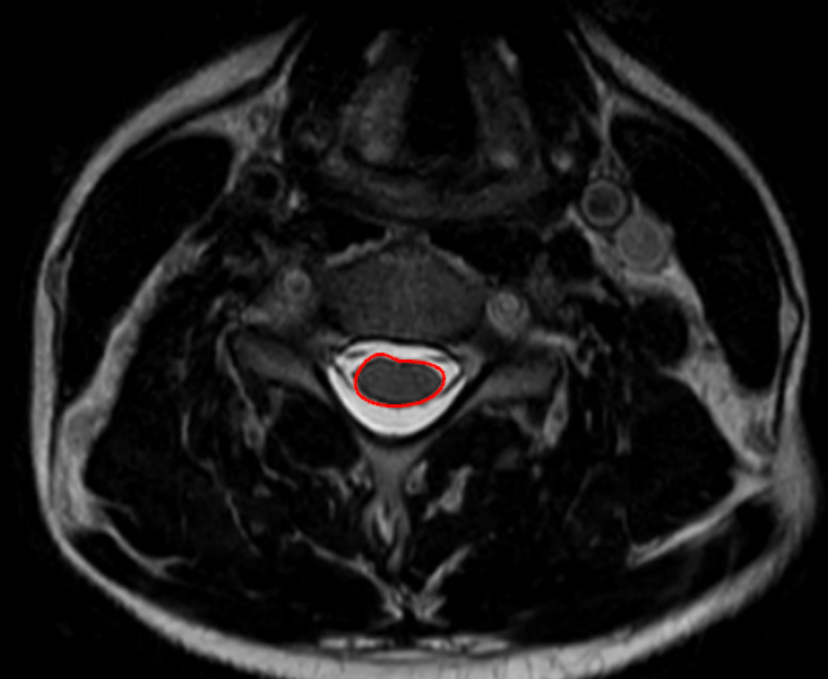

Cord cross-sectional area (CSA) quantifies the total area of the cervical spinal cord on axial MRI and is a direct morphologic marker of cord size, compression, and atrophy.

• Identify the outer boundary of the spinal cord, visualized as the interface between:

• Cord parenchyma (intermediate signal), and

• Surrounding cerebrospinal fluid (high T2 signal)

• Using a freehand region-of-interest (ROI) tracing tool:

• Carefully trace the outer margin of the spinal cord, excluding CSF, dura, and nerve roots.

• Close the ROI to obtain an automated CSA calculation (mm²).